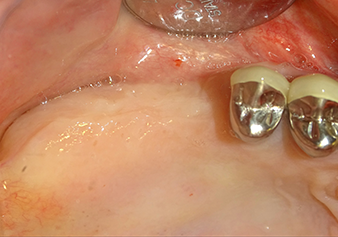

Implantation and prosthetic restoration

To move the augmentation material in the direction of the maxillary sinus atraumatically, the implant was inserted very slowly by hand (Fig. 9). In the process, the membrane was pushed in the cranial direction once again. After two months, the surgical site healed without irritation. Six months later, the x-ray check showed a significant increase in opacity as an indication of ossification (Fig. 10). The prosthetic restoration was carried out with a metal-ceramic crown.

Situation after insertion of the implant

Fig.9: Situation after insertion of the implant (length: 10 mm, prosthetic platform: 6.5 mm) immediately before suturing.